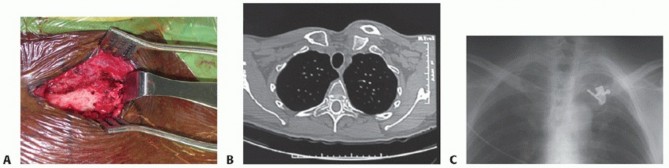

Without question, CT scanning is the best technique to study the sternoclavicular joint. It distinguishes dislocations of the joint from fractures of the medial clavicle and clearly defines minor subluxations (FIG 5). With the increasing presence of O-arms in hospitals, intraoperative CT may become more readily available for both

closed and open reductions.33

FIG 5 • CT scans of a 6-month-old medial clavicle fracture demonstrate anterior displacement without significant healing.*

TECH FIG 5 • Intrasternal Balser (hook) plate insertion.*